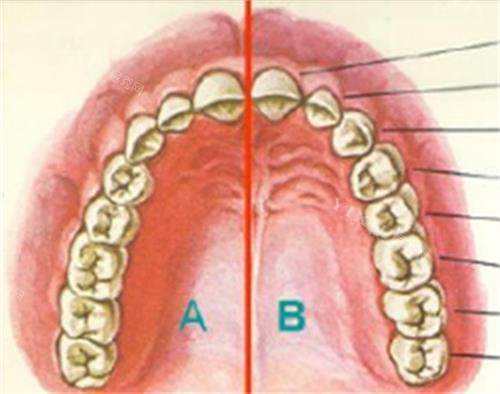

传统种植牙要求牙槽骨至少有8-10mm高度,但上颌骨重度萎缩患者(牙槽骨高度<5mm)根本达不到标准。穿颧种植直接绕过萎缩的牙槽骨,把3-5cm长的种植体植入颧骨(眼眶外下方骨质厚达15-20mm),相当于在“贫瘠土地”上找到了“肥沃新土壤”。